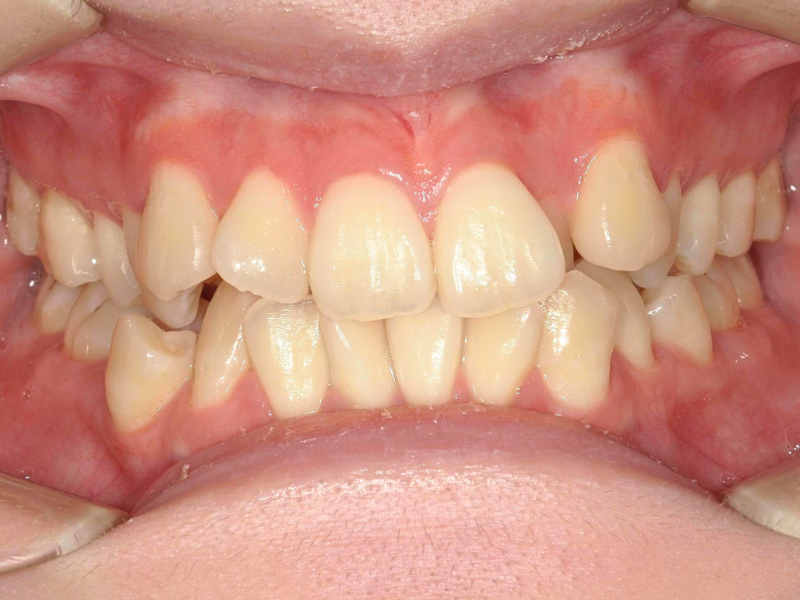

20代、女性、ワイヤー

| 施術内容 | 主訴:全体的に凸凹が気になる 詳細:ワイヤー矯正での歯並び改善 ずっと磨きにくく、臭いが気になっていましたが、 矯正後は磨きやすくなり、臭いも無くなって満足された症例です。 |

| 治療期間 | 16ヶ月(3/13現在 治療終了) |

| リスク・副作用 | ■リスク・副作用 ・治療の初期段階では、痛みや不快感が生じやすくなりますが、一週間前後で慣れます。 ・歯の動き方には個人差があるため、予想された治療期間より延長する場合があります。 |

| 費用 | ワイヤー矯正 60万円(税込660,000円) |